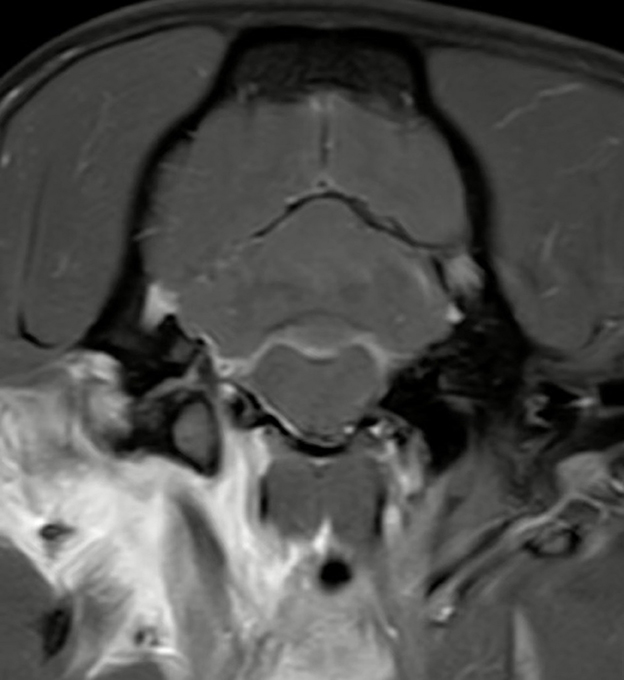

3.4 Meningeal splitting

In up to 13 cases observers detected meningeal splitting (Figures 6–8). This was seen either in both sequences, only in the 3D-GRE-T1W, or only in the FS-TSE-T1W sequence, as shown in Figures 7, 8. It is noted that if meningeal splitting was evident, it was seen most often in both sequences.

Figure 6. Transverse images at the level just caudal to the temporomandibular joints.Example of a case with marked meningeal enhancement and meningeal splitting in a cat. (A) is the T1W-pre-contrast image, (B) the 3D-GRE-T1W and (C) the FS-TSE-T1W.